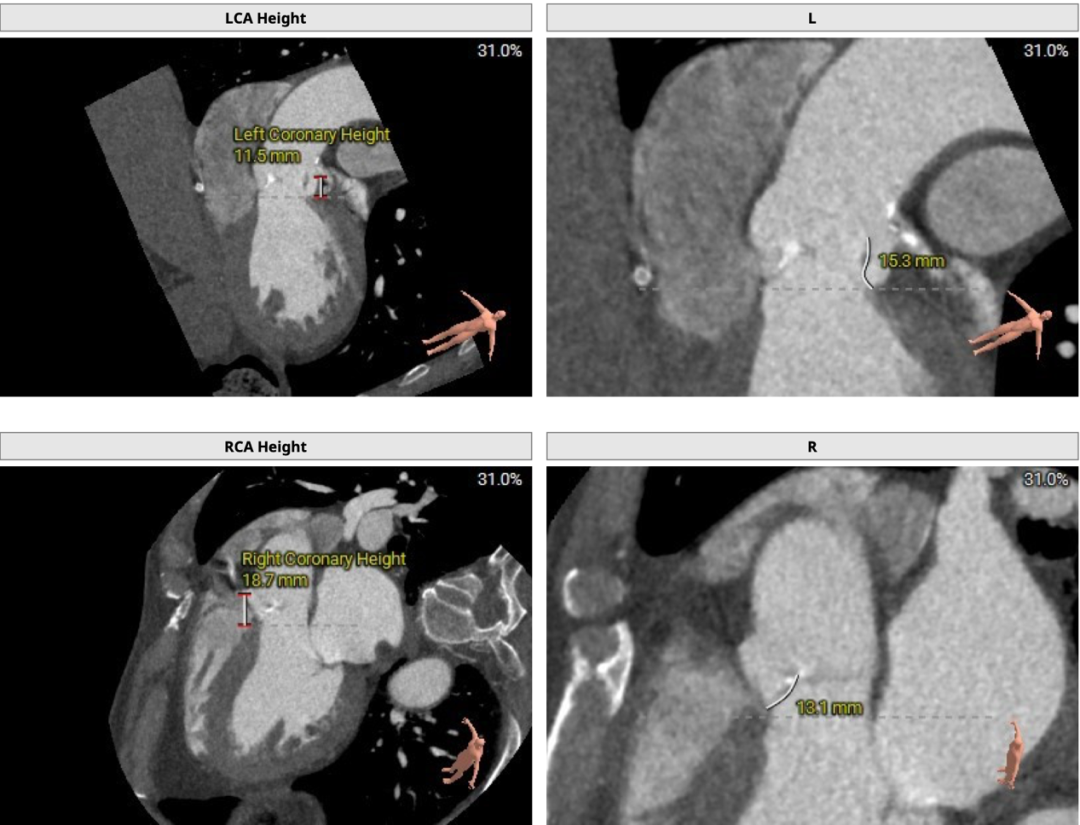

双侧冠脉开口高度可,LCA 11.5mm, RCA 18.7mm;右冠、左冠及分支轻度钙化:

术中建议造影角度LAO 4°,CAU 6°(其它考角度如下图):